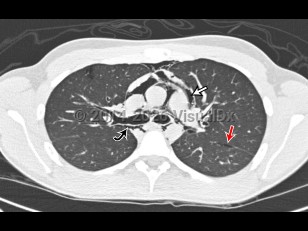

Pulmonary embolismPulmonary embolism